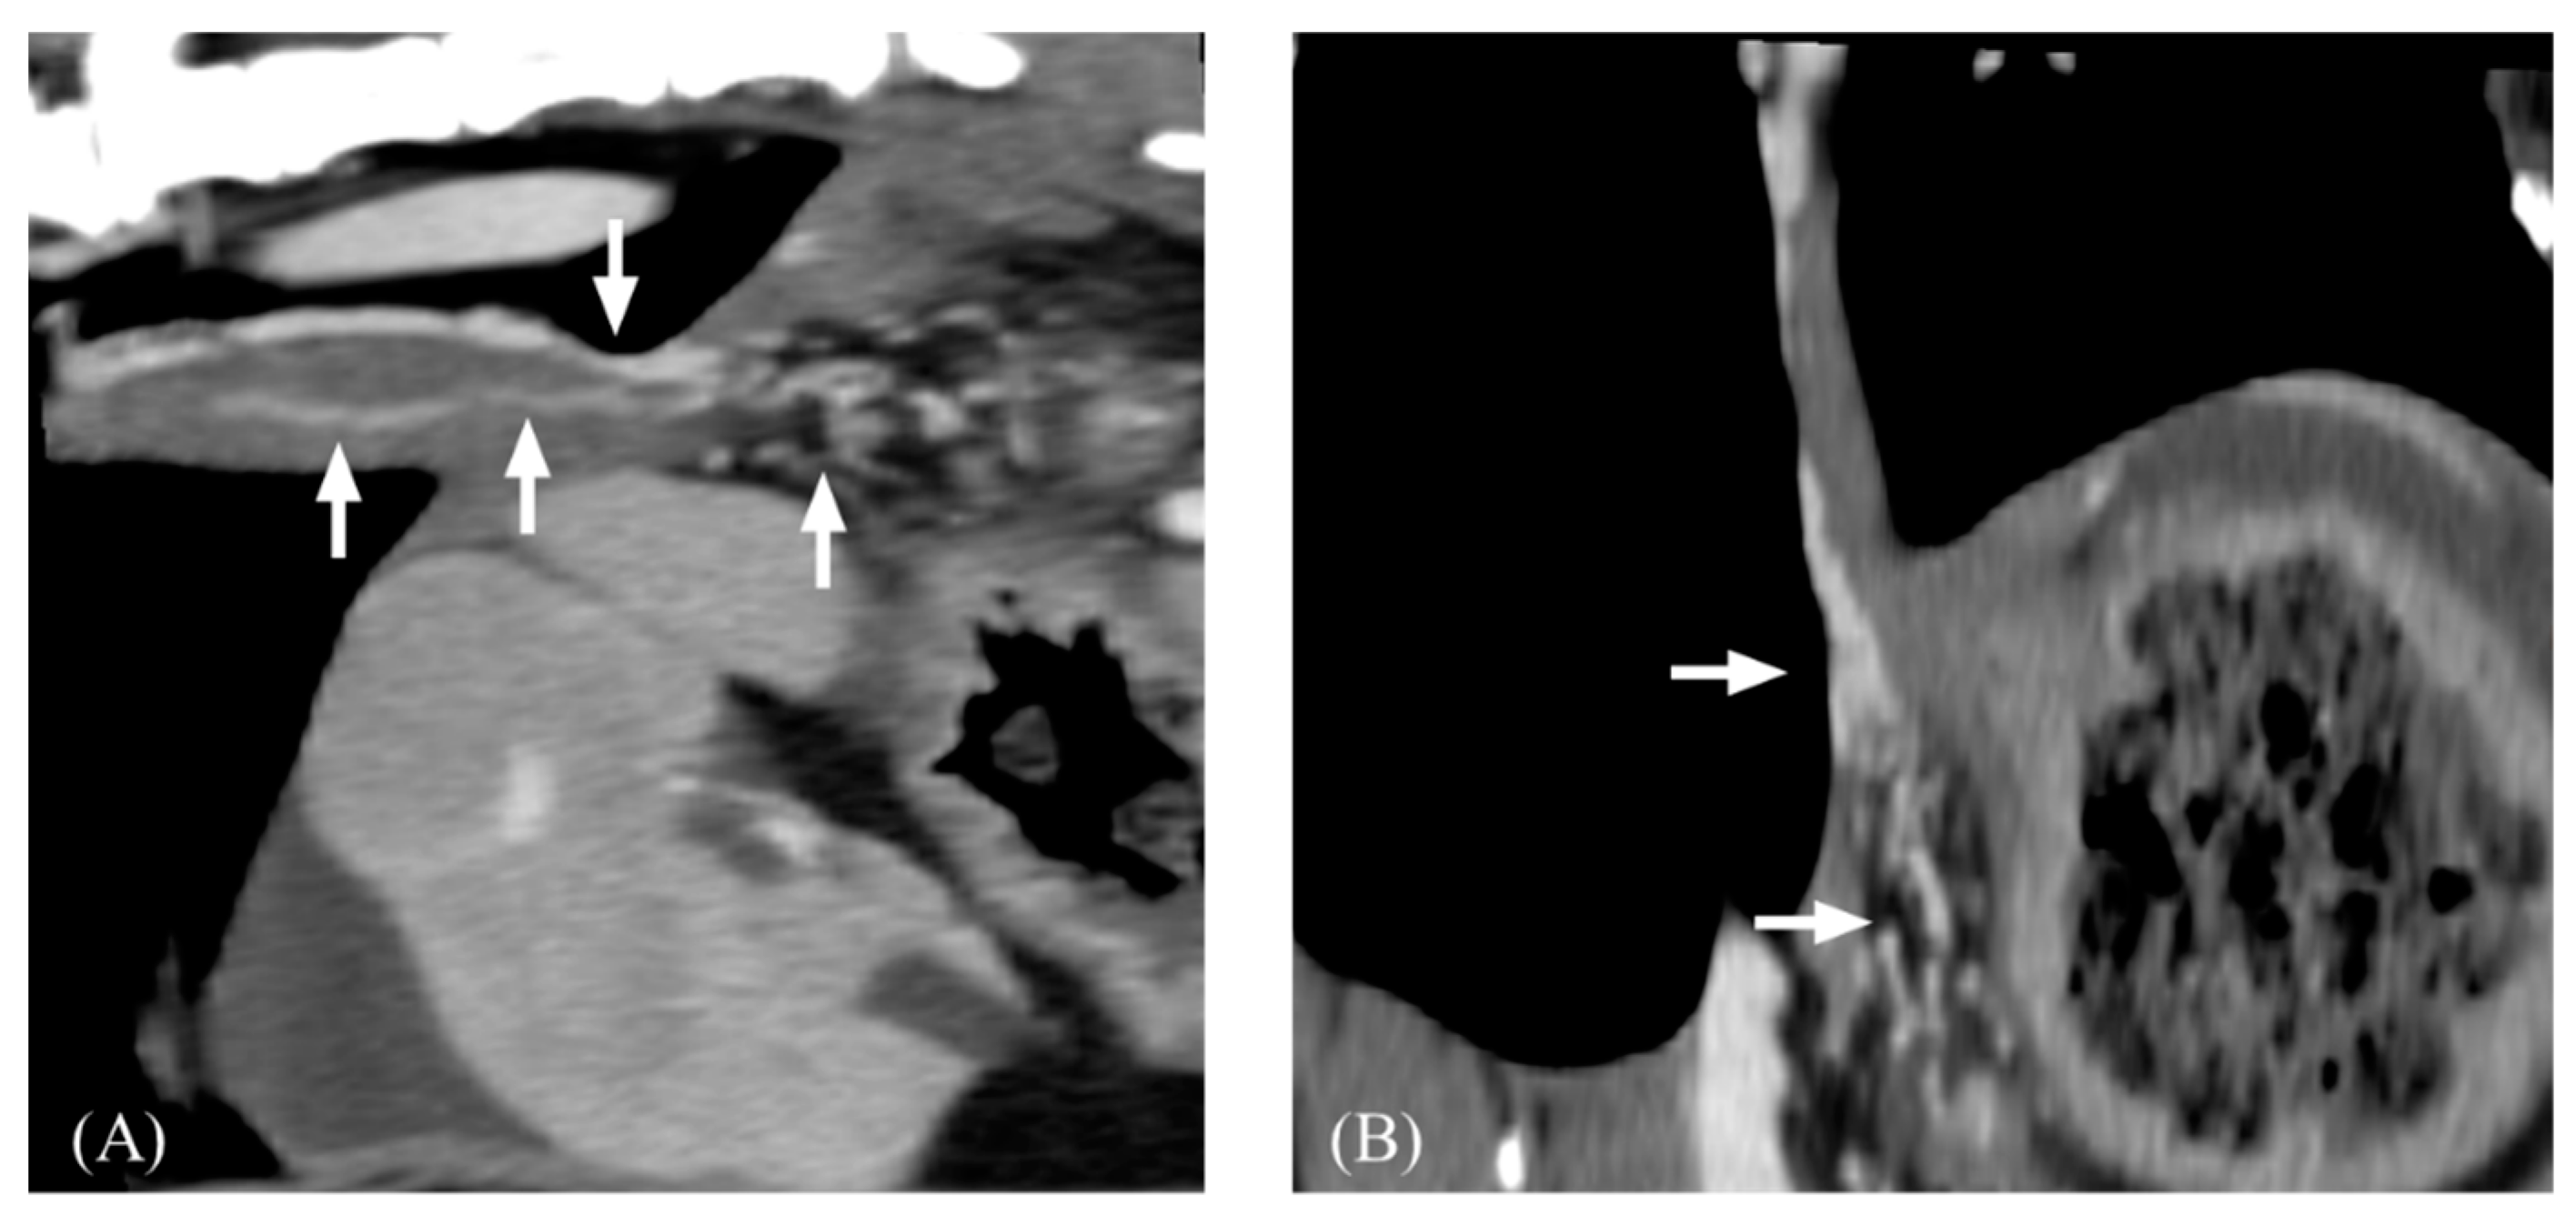

3.2. Qualitative Computed Tomographic Features